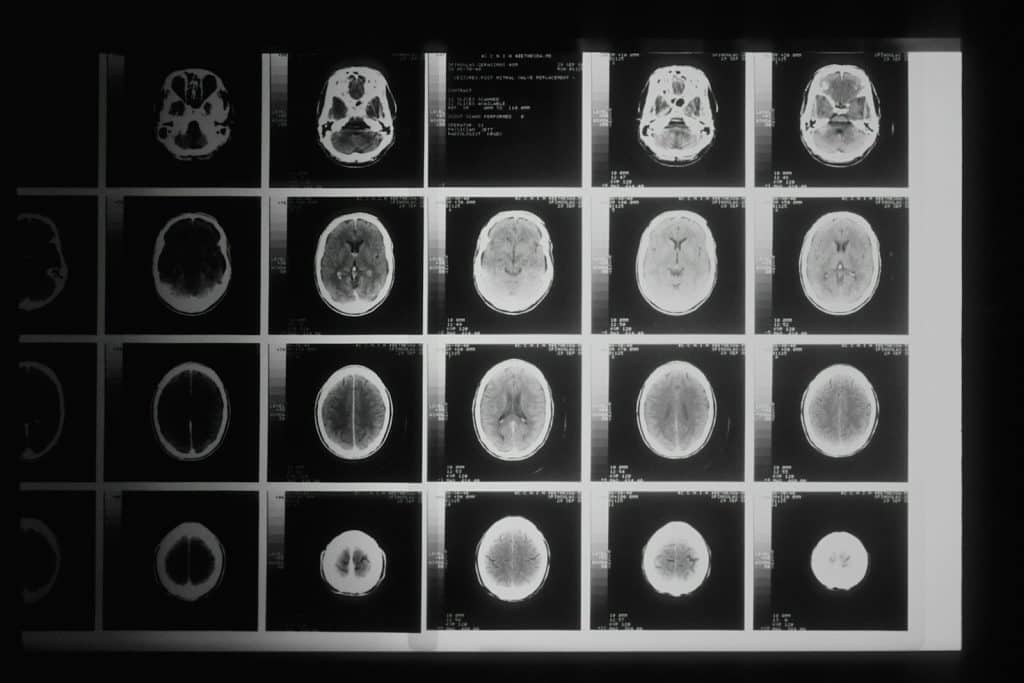

Mokslininkai mano, kad dalis šių mikroskopinių dalelių gali pasiekti smegenis. Tai gali įvykti peržengus kraujo ir smegenų barjerą arba patekus per kvapo nervo ląsteles nosies ertmėje.